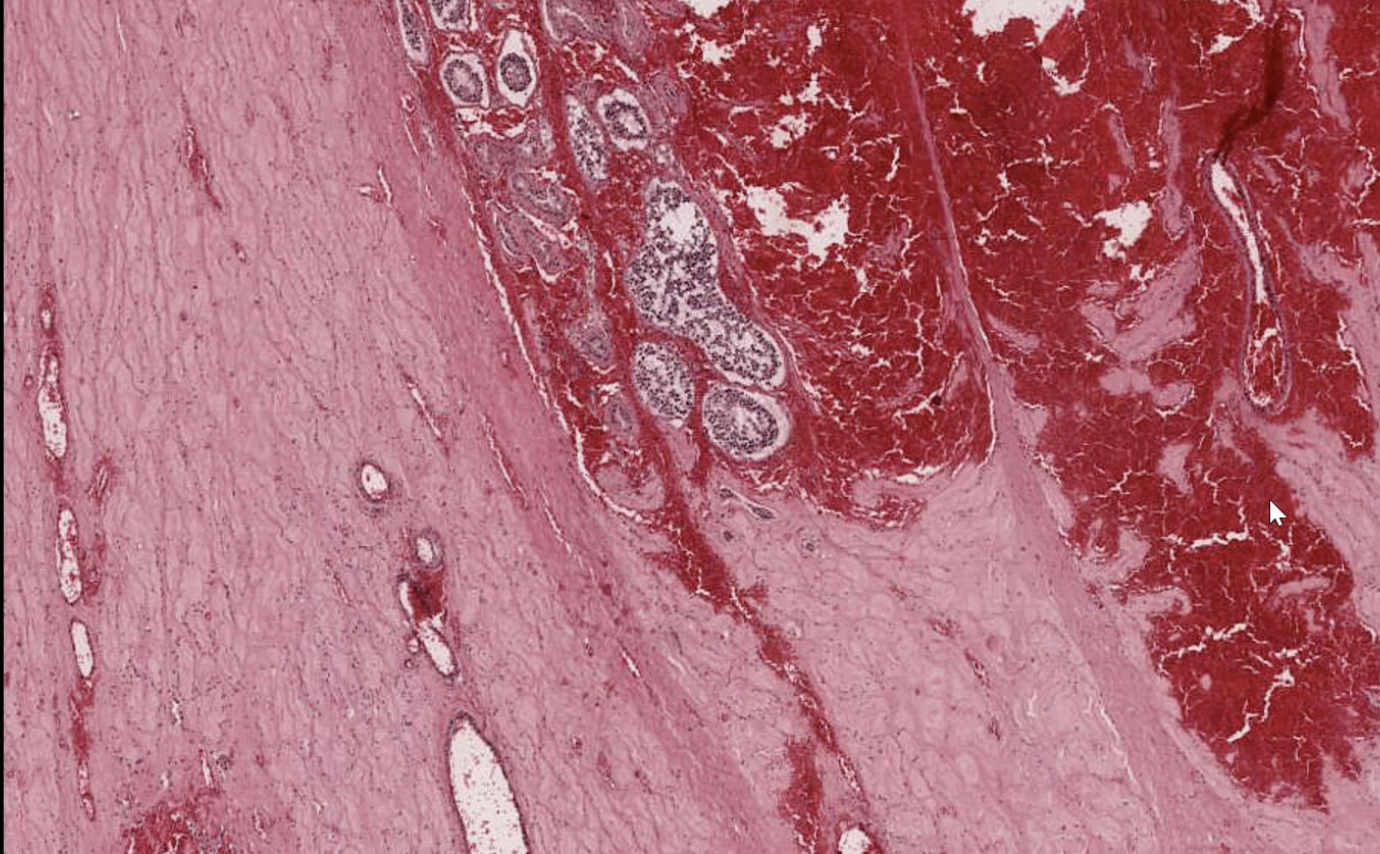

Testicular Torsion